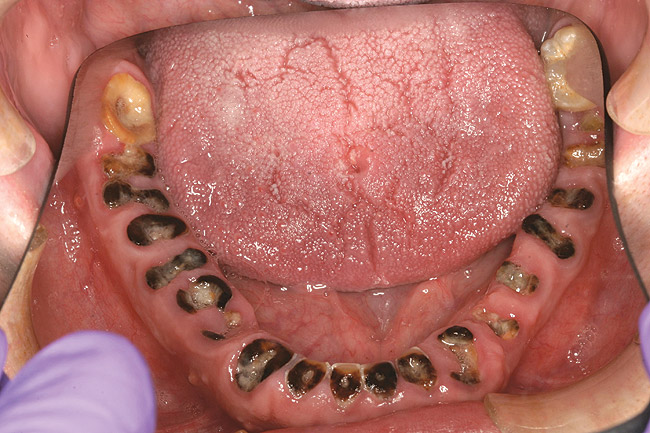

When smoked, methamphetamine produces highly toxic and corrosive fumes of lithium, muriatic, and sulfuric acids that can destroy enamel rapidly. With continued use, methamphetamine can produce severe, rampant caries, similar to early childhood caries. Patients have reported noticing changes in the appearance of tooth structure in as little as 3 months of use. The affected surfaces are the buccal and labial smooth surfaces, as well as the interproximal surfaces (Figure 1 through Figure 3). Because in the general population the vast majority of decay is found in the posterior molars, when someone presents with rampant anterior lesions it should be a red flag for methamphetamine use.5

Figure 1  DEVASTATING EFFECTS When smoked, methamphetamine produces highly toxic and corrosive fumes of lithium, muriatic, and sulfuric acids that can destroy enamel rapidly. With continued use, methamphetamine can produce severe, rampant caries. When someone presents with rampant anterior lesions it should be a red flag for methamphetamine use.

Figure 1

Figure 2  DEVASTATING EFFECTS When smoked, methamphetamine produces highly toxic and corrosive fumes of lithium, muriatic, and sulfuric acids that can destroy enamel rapidly. With continued use, methamphetamine can produce severe, rampant caries. When someone presents with rampant anterior lesions it should be a red flag for methamphetamine use.

Figure 2

Figure 3  DEVASTATING EFFECTS When smoked, methamphetamine produces highly toxic and corrosive fumes of lithium, muriatic, and sulfuric acids that can destroy enamel rapidly. With continued use, methamphetamine can produce severe, rampant caries. When someone presents with rampant anterior lesions it should be a red flag for methamphetamine use.

Figure 3